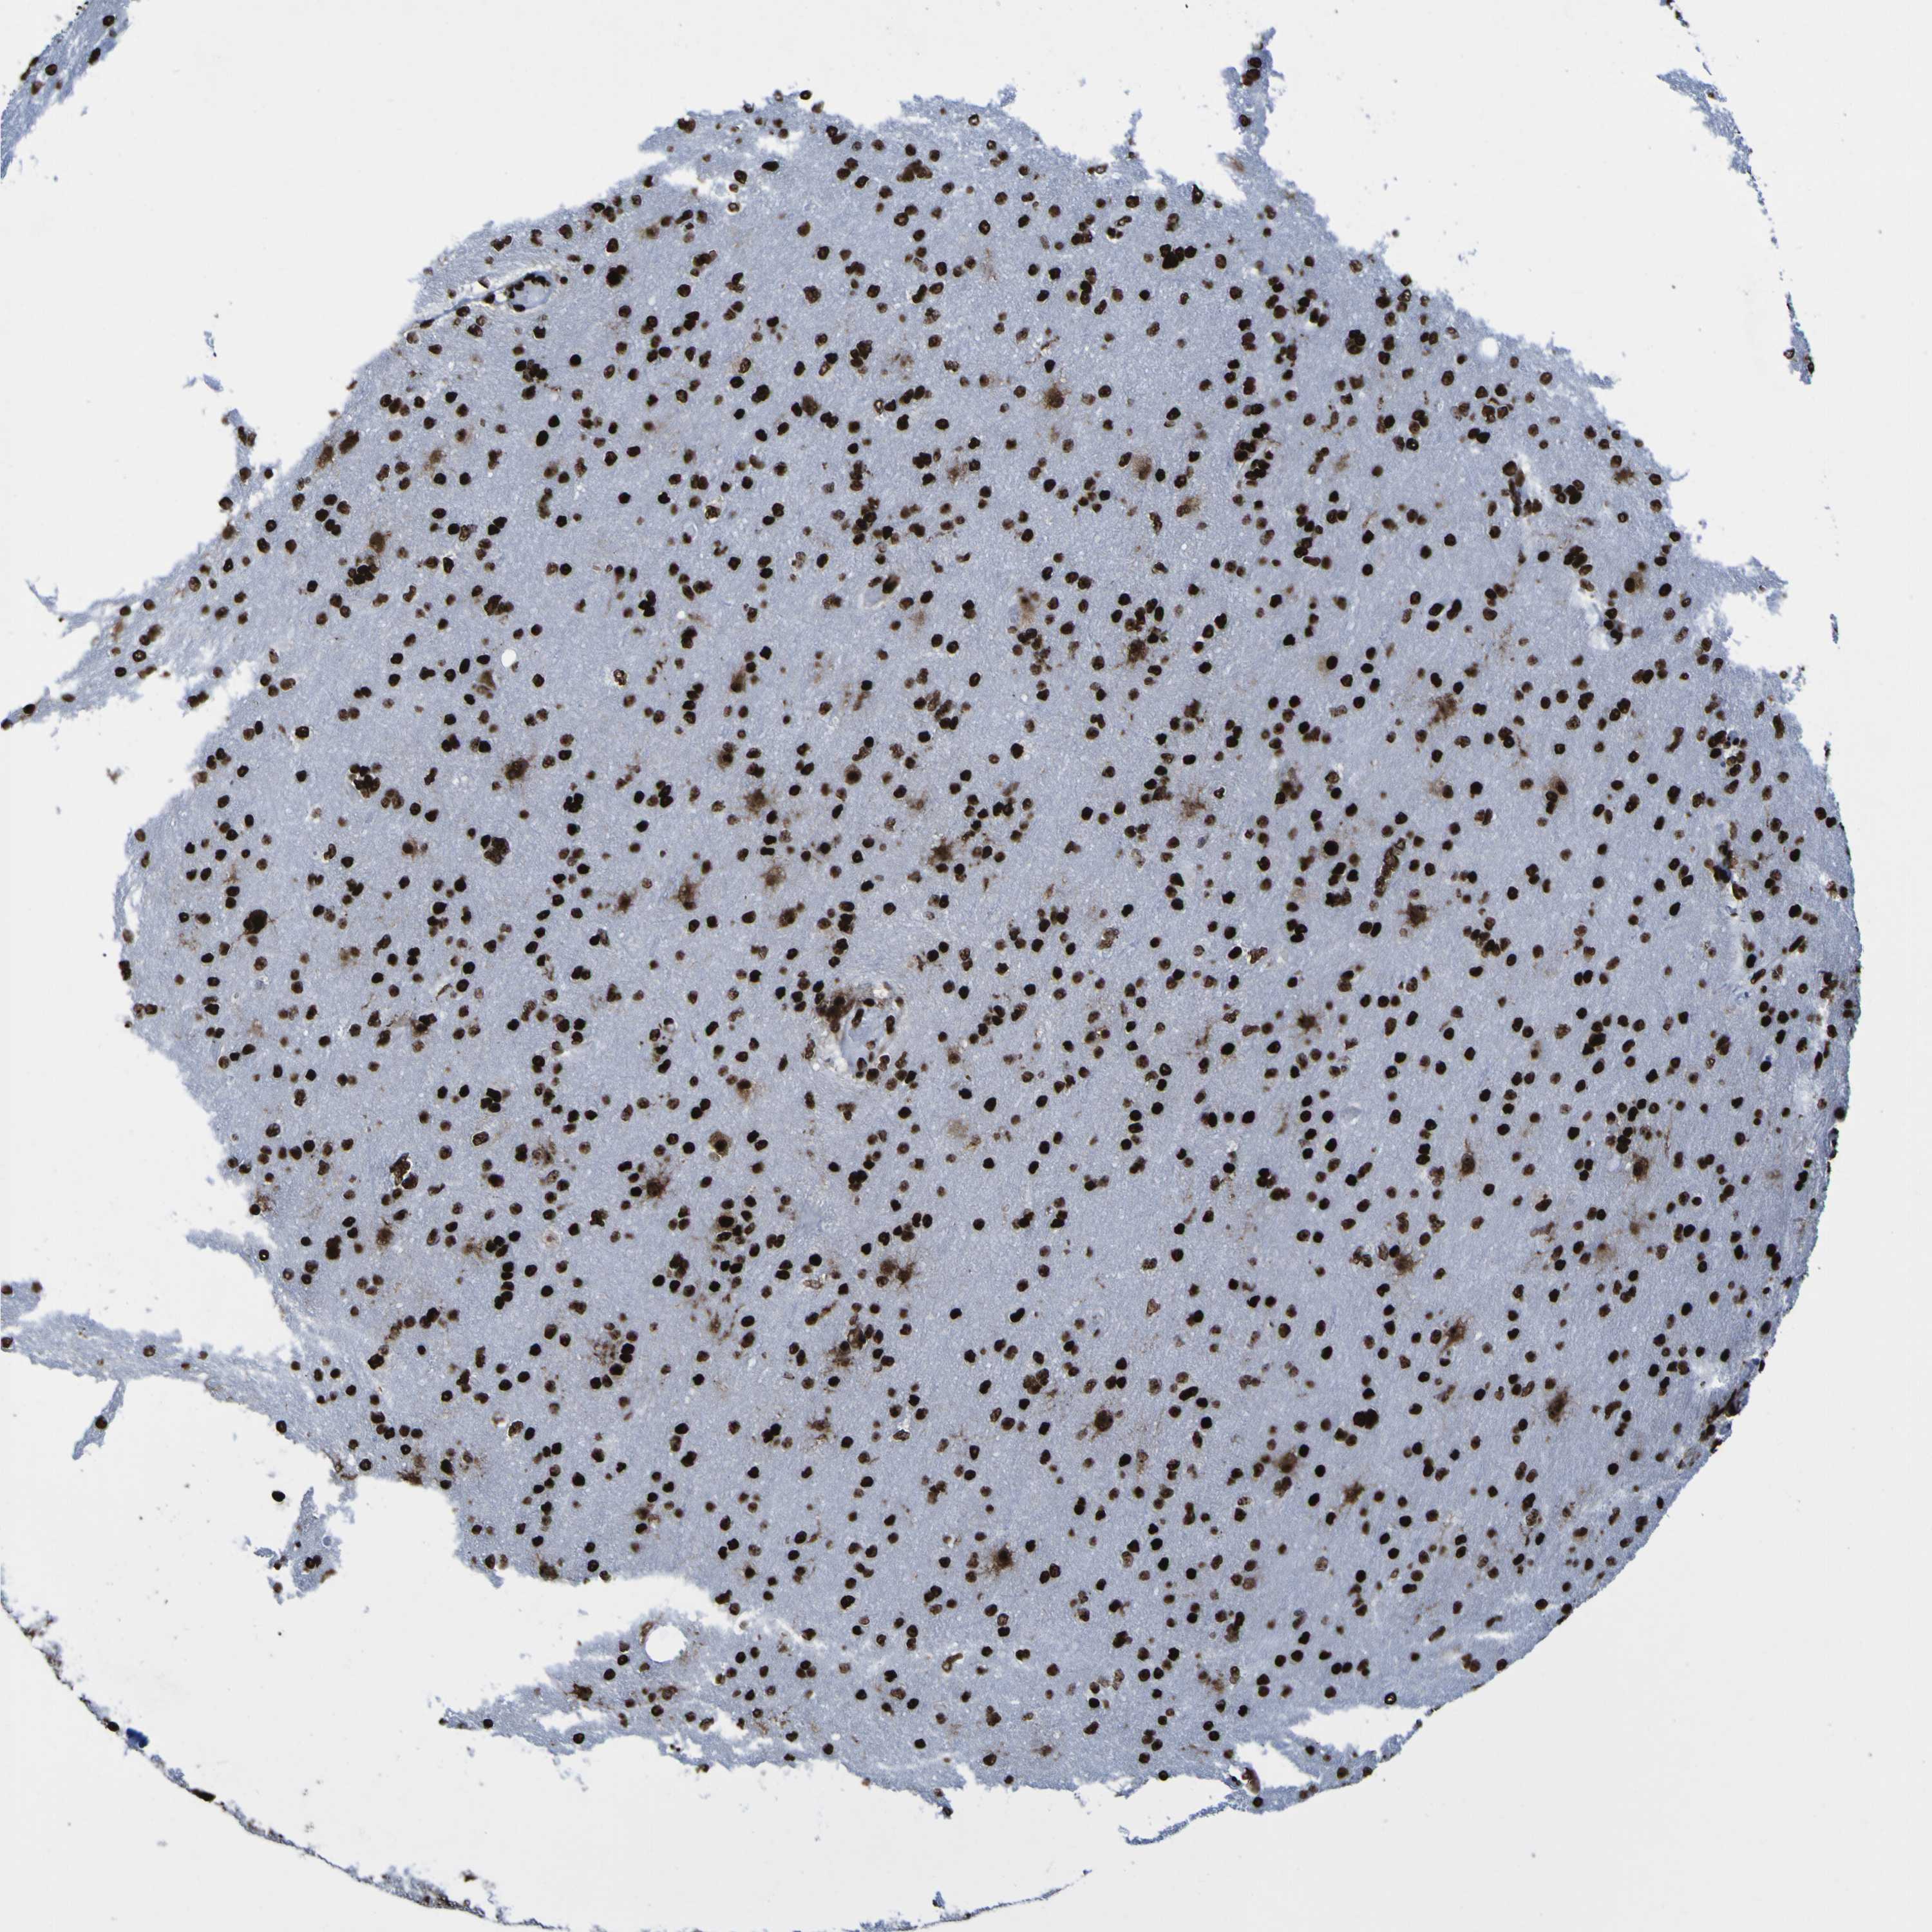

GLIOMA - Protein expressioni

A mouse-over function shows sample information and annotation data. Click on an image to view it in a full screen mode. Samples can be filtered based on level of antibody staining by selecting one or several of the following categories: high, medium, low and not detected. The assay and annotation is described here.

Note that samples used for immunohistochemistry by the Human Protein Atlas do not correspond to samples in the TCGA dataset.

Antibody stainingi

Antibody staining in the annotated cell types in the current human tissue is reported as not detected, low, medium, or high, based on conventional immunohistochemistry profiling in selected tissues. This score is based on the combination of the staining intensity and fraction of stained cells.

Each image is clickable and will lead to virtual microscopy that enables deeper exploration of all samples and also displays staining intensity scores, fraction scores and subcellular localization as well as patient and tissue information for each sample.

Antibody HPA011384

Antibody CAB012983

Staining

High

Medium

Low

Not detected

Intensity

Strong

Moderate

Weak

Negative

Quantity

>75%

75%-25%

<25%

None

Location

Nuclear

Cytoplasmic/membranous

Cytoplasmic/membranous,nuclear

Glioma, malignant, High grade

Glioma, malignant, Low grade